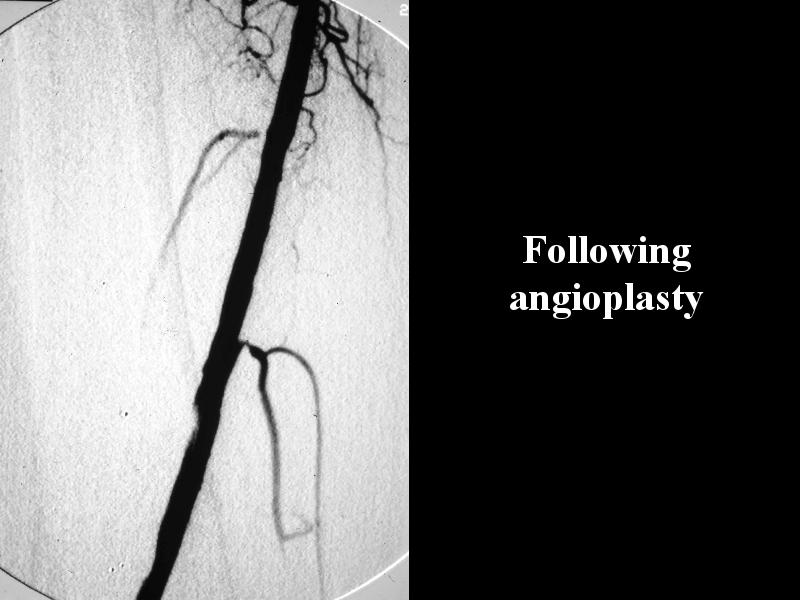

MS 123 POST OP PLASTY